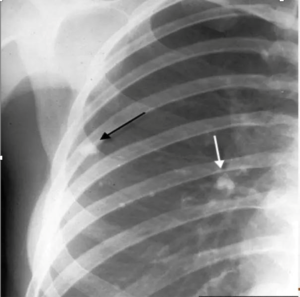

shows a right upper lobe airspace opacity adjacent to the trachea.

• ⁠ ⁠focal or patchy heterogeneous consolidation involving the apicoposterior segments of the upper lobes and the superior segments of the lower lobes

lateral view of the same patient, the typical location of the apicoposterior segment

• ⁠ ⁠Xray showing cavitatory consolidation in right upper lung zone and multiple ill-defined nodules in both lungs

CAVITATION AND TREE IN BUD SIGN IS INDICATIVE OF AN ACTIVE DISEASE PROCESS AND USUALLY HEALS S A LINEAR OR FIBROTIC LESION.